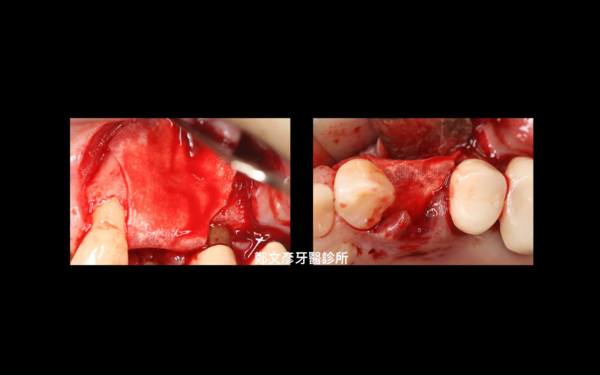

Role of granulation tissue in socket preservation

3. Role of granulation tissue in socket preservation